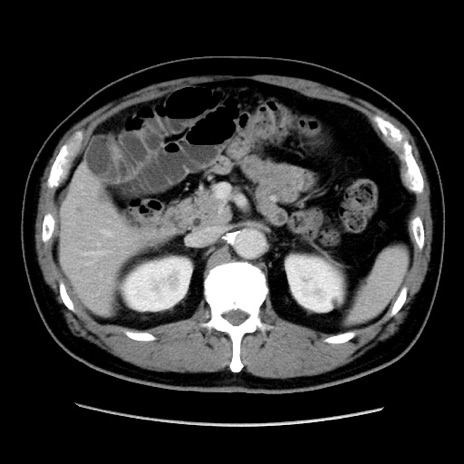

症例16(横断像)

【症例】 70歳代男性

【主訴】 腹痛、嘔吐

【現病歴】 約1ヶ月前より間欠的に腹痛と嘔吐あり、当院消化器内科を受診したところCTで多発する肝臓のLDAを指摘され、精査中であった。以降は消化器症状は安定していたが、2日前より嘔気と腹痛があり、同日より排便・排ガスが消失した。改善認めず、 本日、救急外来を受診した。

【身体所見】意識清明・会話良好、BT 36.3℃、BP 127/80mmHg、 P 80bpm、腹部:膨満あり、平坦・軟、上腹部正中および下腹部正中に圧痛あり、反跳痛なし、筋性防御なし。

【データ】WBC 7200、CRP 0.77